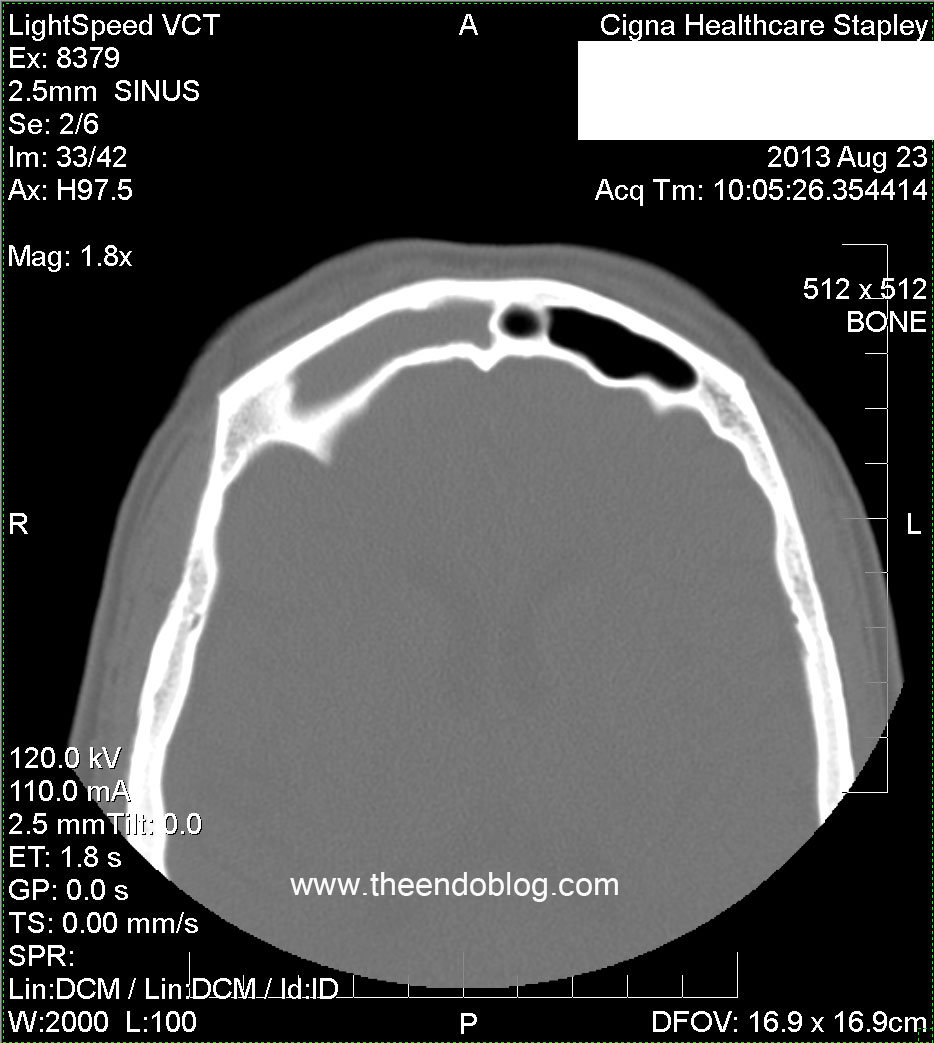

RADIOGRAPHIC FINDINGS:

Complete opacification of the right frontal sinus.

Partial opacification of the R ethmoid sinuses.

Complete opacification of R maxilliary sinus, superior septal deviation to the right, bilateral opacified concha bullosas.

Molar #2 and #3 have periapical radiolucency (PARL), one of which is dehiscent into the maxillary sinus and buccal gingival sulcus.  This may be the most important diagnostic information in the CT scan.  Too often, radiologists and otolaryngologists are not looking at this part of the scan - if it is even included in the field of view.